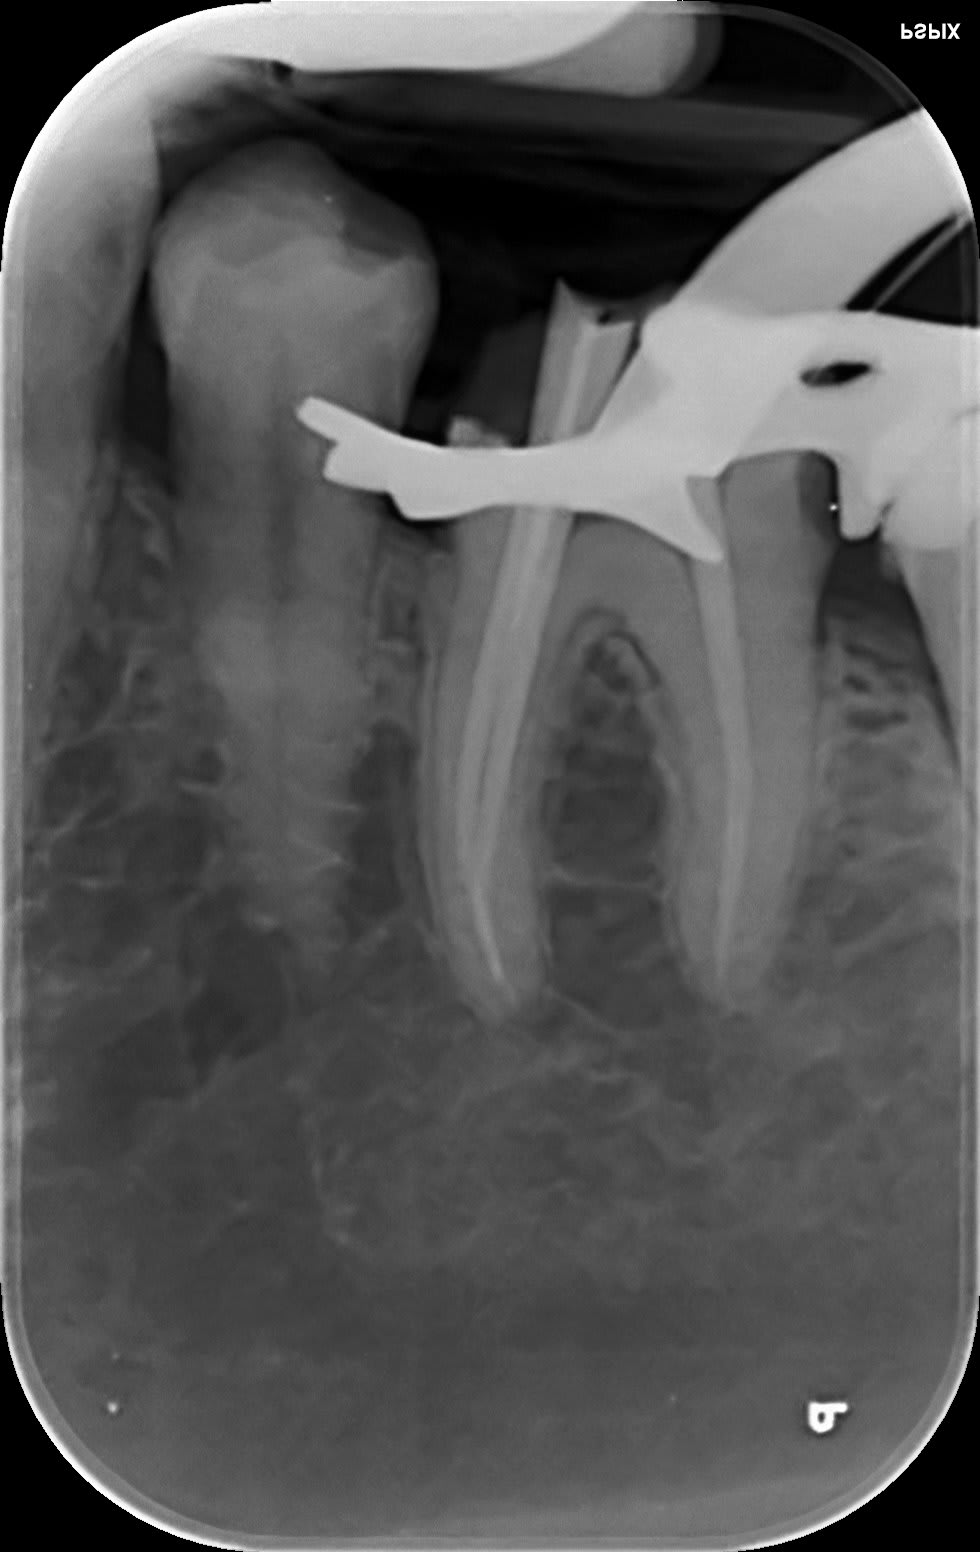

et puis finalement, limes k... protapers golds... R25 blue... US...

cones en place c'est acceptable, c'est bien d'avoir du temps et du matos.

C'est bien d'avoir mis la digue aussi...

c'est pas l'endo du siècle, mais le canal (les ..?) latéraux en distal y sont, le localisateur d'apex les avait bipé et en mésial on est pas si mal, c'est la qualité de la radio qui est trompeuse... il faut que je recalibre les expositions.

0.88 c'est la mesure la plus défavorable, la plus favorable donnait 0.15 par rapport à l'apex radiologique et le réciproc donnait toutes les barres avant apex.